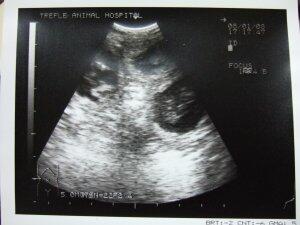

エコー写真

病院でもらったエコー写真です。

黒い丸が三つ。

今のところ、三匹いるようです。

この黒丸が、もうすでに可愛く思えるんですが・・・。